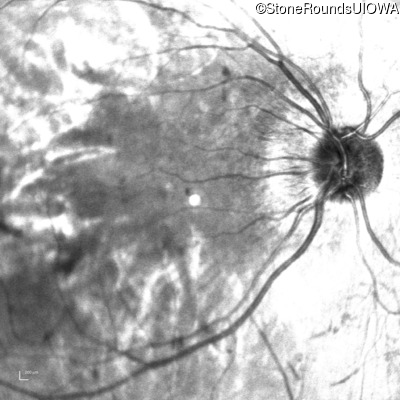

Infrared Fundus Photograph - Right - 20/200 -1

Exemplar